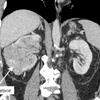

Nesta semana, em Itaperuna, Rio de Janeiro, uma mulher passou por uma cirurgia de emergência para a retirada de um tumor de 46 kg. A paciente de 45 anos pesava 150 kg e tem 1,52 metro de altura. Apesar da gravidade do caso, ela está internada e passa bem.

Segundo o médico-cirurgião que realizou o procedimento, foi um dos maiores tumores que alguém já operou. "Foi o maior tumor que eu operei e certamente um dos maiores que alguém já operou. Não é todo dia que se faz uma cirurgia de um tumor desse tamanho, não", disse Glaucio Boechat, ao site UOL.

O procedimento para a retirada do tumor iniciou após a mulher dar entrada no Hospital São José do Avaí, sentindo falta de ar ocasionada pelo tumor que ela tinha há cinco anos. Feitos exames, a equipe médica optou pela cirurgia de emergência. O médico com mais de 20 anos de carreira conta que o procedimento demorou cerca de duas horas.